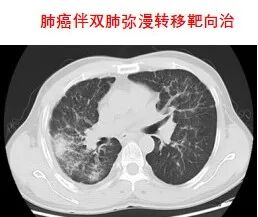

放射治療是利用高能放射線消滅腫瘤的原發灶或轉移灶的一種局部治療方法。是治療惡性腫瘤的三大手段之一,具有無創、副作用小、適應范圍廣、腫瘤局部控制率高等優點。適應癥:全身各部位早、中、晚期惡性腫瘤。

3.分子靶向治療

4.免疫治療: